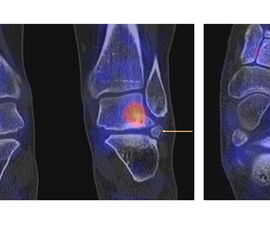

Die Abbildungen 4.2.a bis d zeigen den typischen Aspekt einer talacalcanearen Coalitio. Es besteht nur eine linksseitige, symptomatische Coalitio talocalcaneare (4.2.a und c); das 35 Tage zuvor angefertigte MRT zeigt keine auffälligen Signalveränderungen (4.2.b und d).

Abbildung 4.3. zeigt die Ursache für rechtsseitige Sprunggelenksbeschwerden bei einem Patienten mit talocalcanearen Coalitionen: nur die osteochondrale Läsion an der distalen rechten Tibia ist die Ursache des Schmerzes. Die bilateralen talocalcanearen Coalitionen sind asymptomatisch.